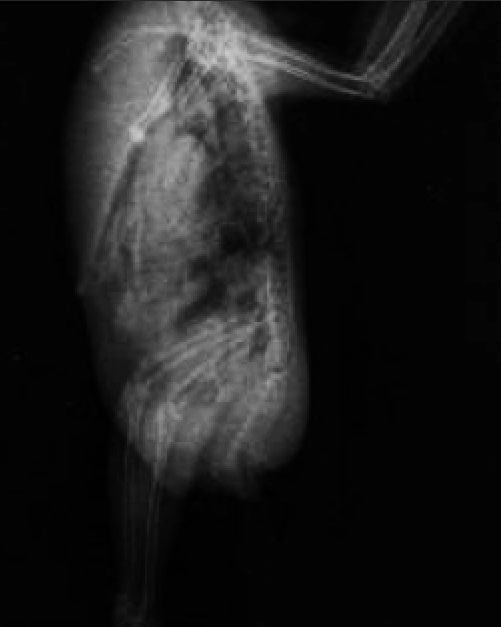

На ВД проекции в брюшной полости фиксируется округлое образование с капсуле, не являющееся желудком. Оно же видно (туманно) и на латеральной проекции. Так же возможно есть еще пара таких образований в зоне расположения яичника.

Так как сезон размножения давно прошел- можно предположить нечто вроде кистозных образований, которые вероятно пережимают нервы, идущие к нижним конечностям.

Покупайте

Ампульный глюканат кальция

Преднизолон (ампульный чел, или ветеринарный Преднивет),дозу напишу в личку.

Диакарб (таблетки).

НПВС- мелкосикам или ибупрофен (ищите в форе суспензий,что у вас есть-не знаю).

Ригевидон таблетки.

ВЕС птицы- точный.

2020-09-14_19-16-55.png

2020-09-14_19-15-55.png